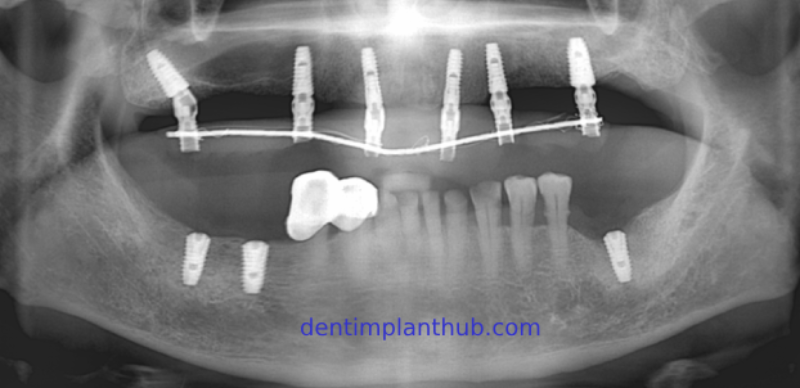

Panoramic radiograph taken for re - examination after the completion of the implant surgery

Panoramic radiograph for re - examination 7 months after the completion of the implant surgery